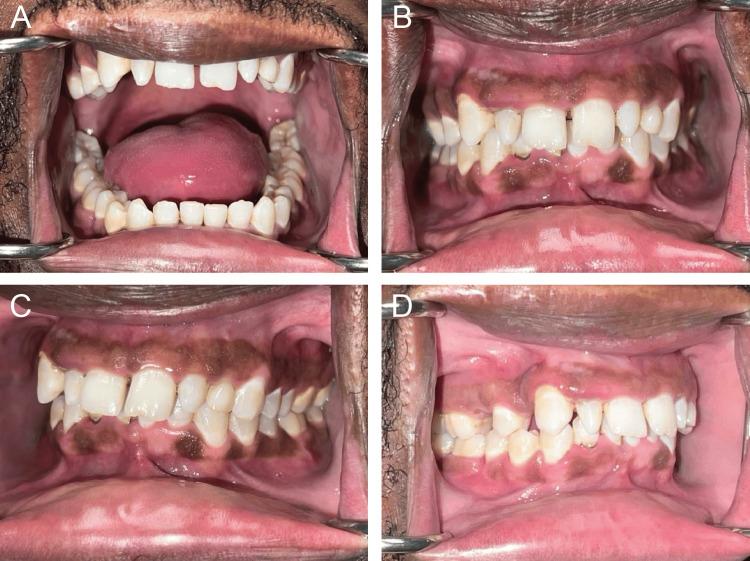

Mandibular fractures are one of the most common types of facial fractures and often result from trauma to the head and neck region. Understanding the mechanism-based factors resulting in different patterns of mandibular injury is important for their surgical management. This study reports a unique mandibular fracture whereby the symphysis and bilateral mandibular bodies were fractured following a gunshot wound to the maxillofacial region. A literature review of case reports on bilateral mandibular fractures highlights the uniqueness of the presented case and supplements the text as the initial management, treatment, and prognosis of the case are discussed.

下颌骨骨折是最常见的面部骨折类型之一,通常由头颈部区域的创伤引起。了解导致下颌骨损伤不同模式的基于机制的因素对于其手术治疗很重要。本研究报告了一例独特的下颌骨骨折,即颌面部区域枪伤后颏部和双侧下颌体骨折。对双侧下颌骨骨折病例报告的文献综述突出了本病例的独特性,并在讨论该病例的初始处理、治疗和预后时对正文进行了补充。